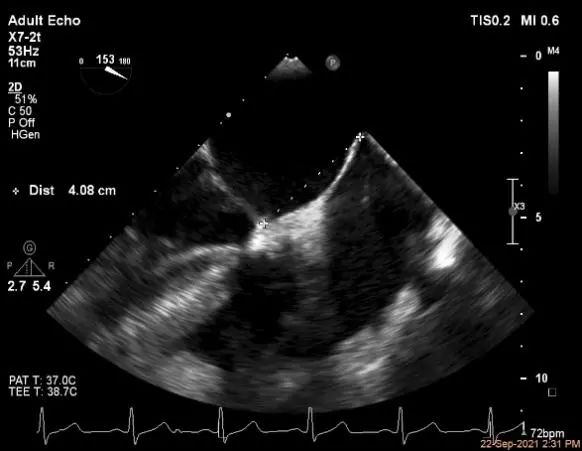

穿刺高度:4.08cm

房间隔穿刺点选择